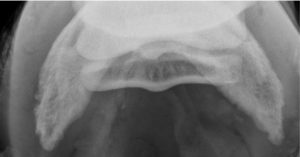

Horses that block to the heel region should have a complete radiographic series performed first. In most instances this is sufficient to help start a treatment plan. In some cases, when no abnormalities are seen, MRI is needed to provide a specific diagnosis which allows us to create a tailored treatment plan. While MRI is costly, the information that can be gathered from this imaging modality can have tremendous benefits in long term treatment planning.

To give an example; a 10-year-old Warmblood gelding presented with bilateral (both) forelimb lameness that blocked to the heel region. Radiographs of the front feet show that the external hoof balance is good but based on the radiographs some minor modifications were needed. There was minor sclerosis of the distal border of the navicular bone. In addition to the shoeing recommendations, the horse was given a single injection into the coffin joint since medications delivered here also diffuse into the navicular region. A short course of oral firocoxib (Equioxx) was prescribed for 14 days. Since on the radiographs the horse had some bone remodeling, we followed up with Osphos every 6 months to reduce bone resorption and modeling over the long term.